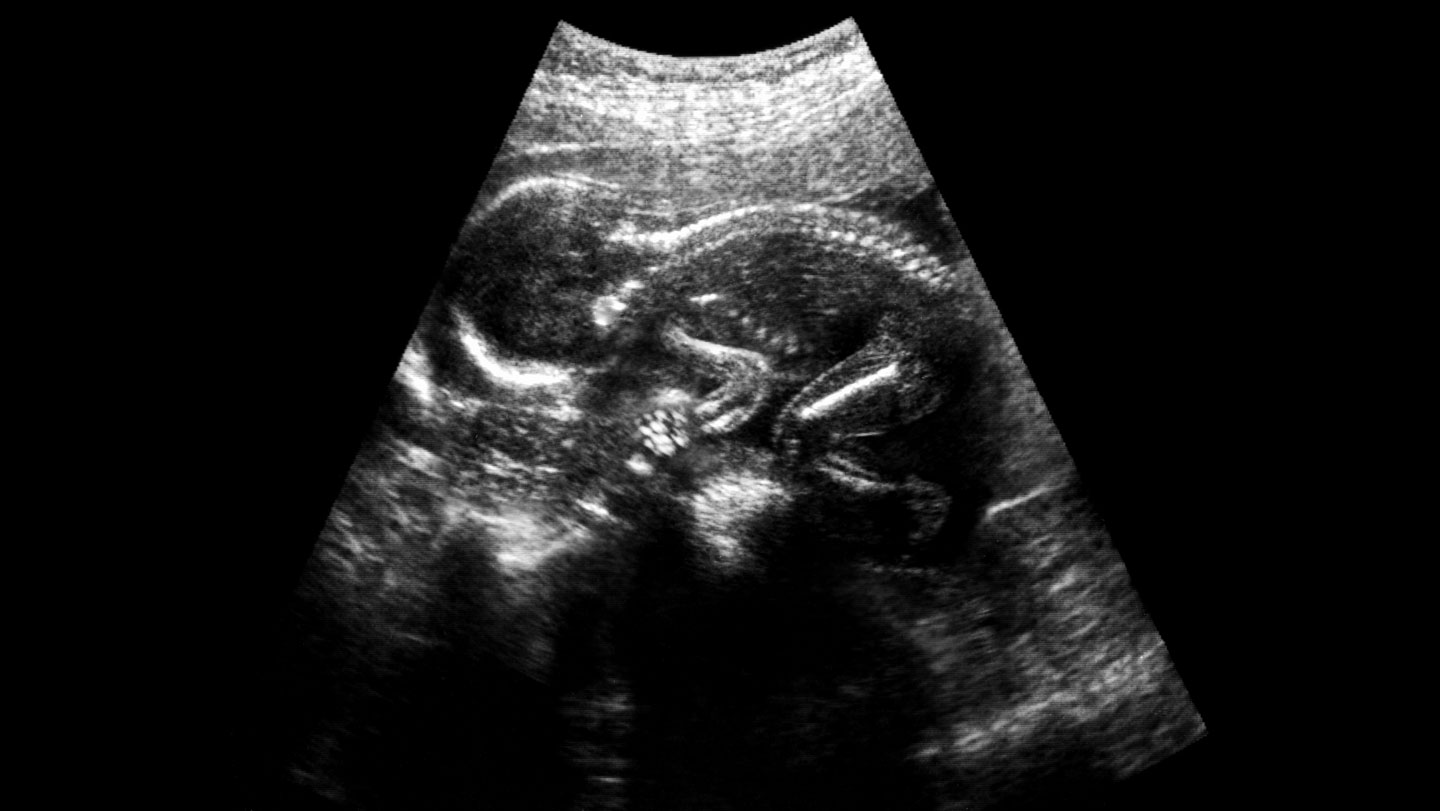

Prenatal surgery for spina bifida may get a boost from stem cells